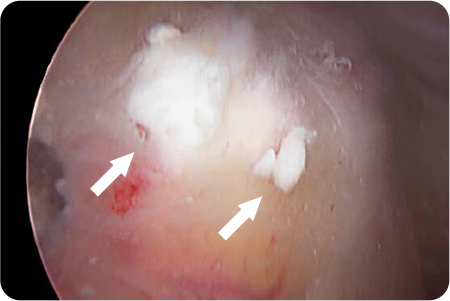

관절경하

석회제거술

어깨 힘줄 조직에 석회질이 침착하여 발생하게 되는

석회성건염이 있을 때 시행하게 됩니다.

관절경을 이용해 석회주변부에서 염증이 생긴

점액낭을 제거함과 동시에 석회 침착물을 제거

합니다.